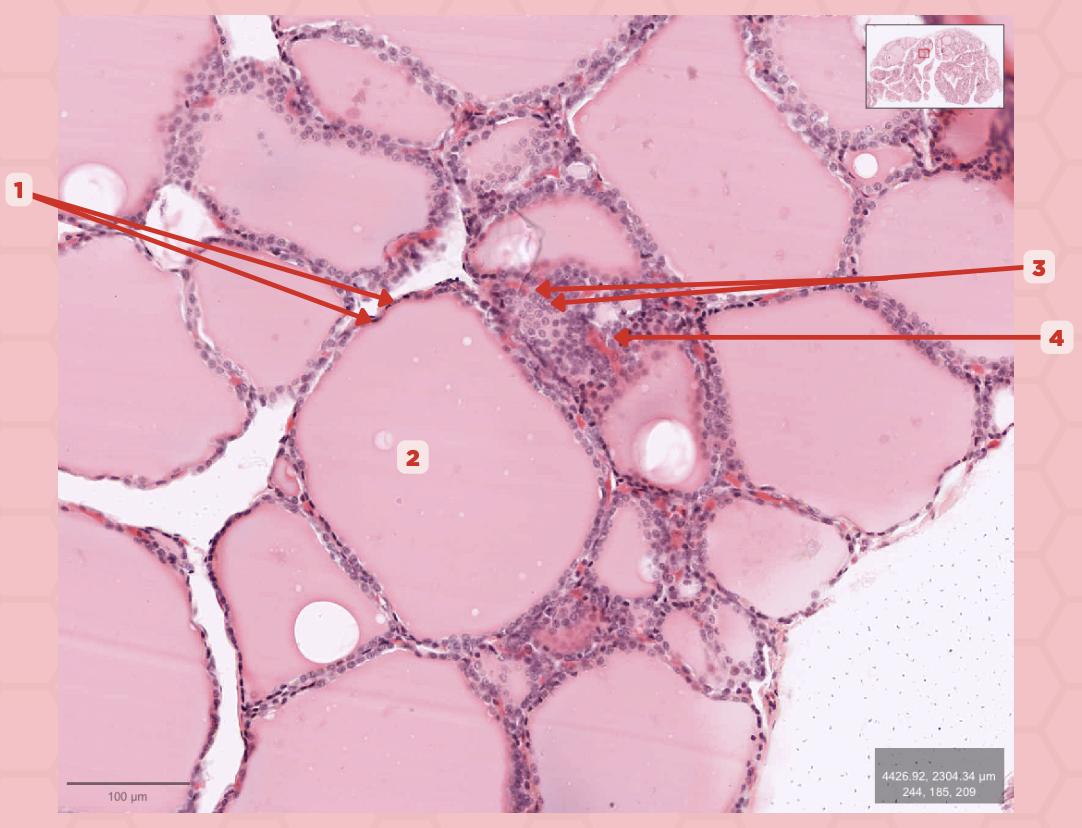

T3 and T4 Hormone

What type of hormone is being secreted by the pointer #1?

Follicular Cells

Identify the structure labeled as 1.

Colloid

Identify the structure labeled as 2.

Parafollicular Cells

Identify the structure labeled as 3.

Capillary

Identify the structure labeled as 4.